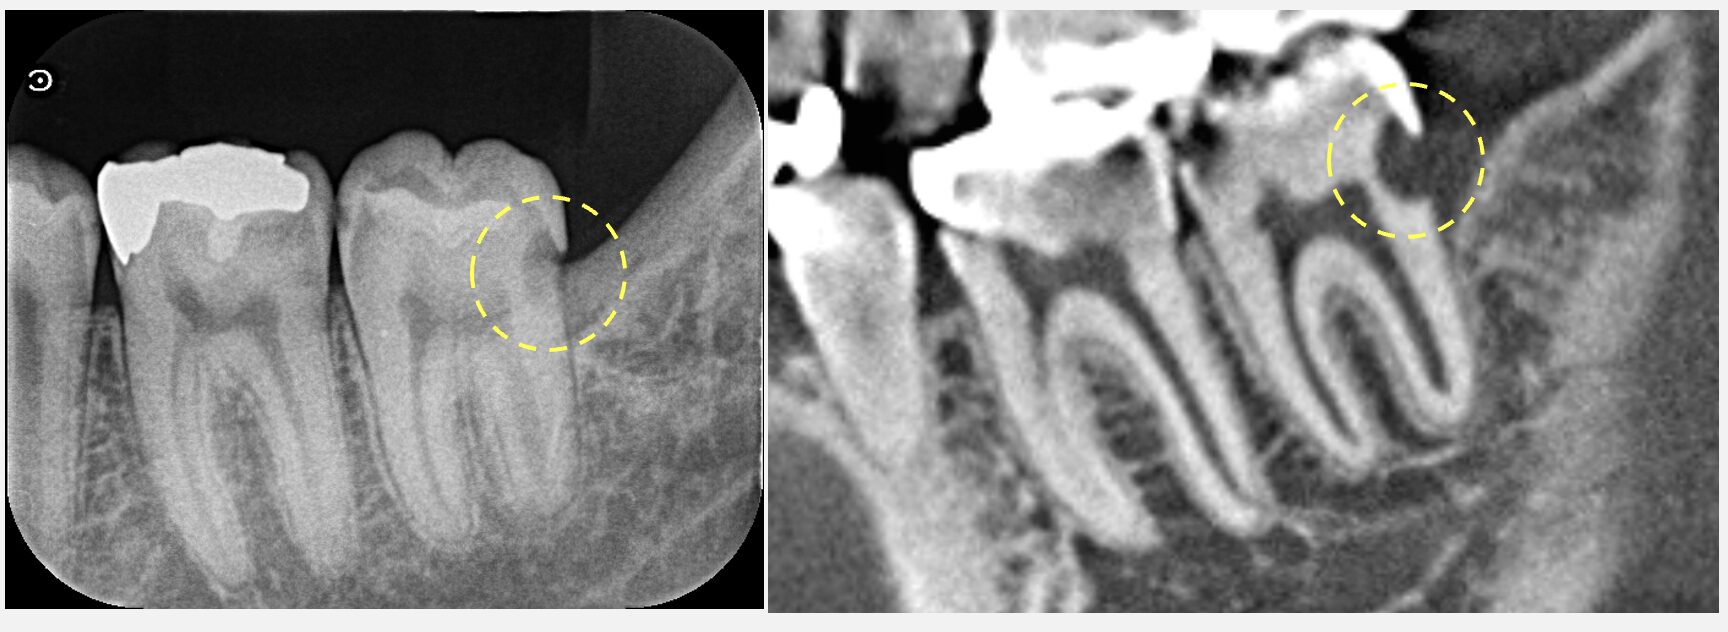

2週間前に、他院で左上7番(一番奥の歯)の治療を受け、その後も痛みが継続しているとのことで来院されました。来院時には痛みが強く、自発痛(何もしなくてもズキズキと感じる痛み)が生じており、神経が炎症を起こしている状態と診断しました。歯の神経の保存は不可能であり、根管治療を行い、まずは痛みを取り除くことを第一優先に治療を行うことになりました。

承知いたしました。通常、”初めて根の中を触る歯”の場合、1回で治療を終えることができます。ただ、⚫️⚫️様の場合、強い痛みがあるという点と、根の中がやや複雑な形をしていそうという点から、治療回数は2回いただければと思います。